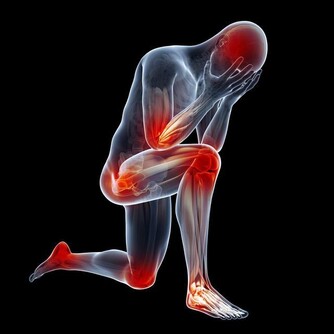

頻繁夜尿會帶來哪些危害?

1、誘發抑鬱症

經過研究發現。晚上頻繁起床夜尿的人,可能也會增加患有抑鬱症的風險。

2、誘發心腦血管意外

如果在晚上睡覺過程當中,頻繁起夜,尤其是在睡夢當中突然地起床,更會導致血壓短時間內升高,心跳加速,也會增加患有心腦血管疾病的風險。

3、導致睡眠障礙

如果在晚上睡覺過程當中,頻繁地起夜,就會影響到正常的睡眠,以至於醒來之後再難以入睡,引發睡眠障礙。

4、易出現跌倒的骨折

如果在晚上睡覺過程當中頻繁地起夜,照明不足的話,再加上因為尿急立即跑到衛生間,稍有不慎可能就會因為跌倒,而造成骨折的風險。